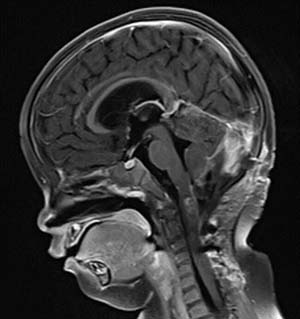

術(shù)后影像(MRI)

然而術(shù)后恢復之路仍充滿波折。因并發(fā)腦積水,患兒出現(xiàn)嘔吐等癥狀,經(jīng)脫水治療效果不佳。醫(yī)療團隊與家屬充分溝通后,再次為阿什利施行腦室-腹腔分流術(shù),術(shù)后腦積水顯著改善。與此同時,醫(yī)院為她制定并實施了系統(tǒng)化療方案,歷經(jīng)5個周期的藥物調(diào)整與精心治療,至今年7月MRI復查顯示術(shù)區(qū)強化灶已完全消失。